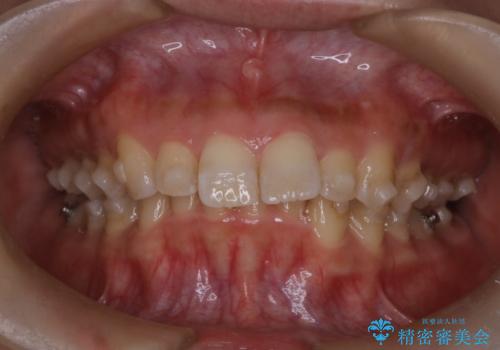

- 上の前歯の出っ歯と前歯の深い咬み合わせを治したいとのことで来院された患者様です。

上顎の歯は後方移動とIPR(歯と歯の間を削る)によって口元が引っ込むように、下顎は歯列全体の拡大とIPRによって上顎とバランスよく咬み合うように設計し、インビザラインにより治療を行うこととしました。

上顎歯列の後方への移動量が多く、右側の奥歯の咬み合わせを改善する必要もあったため、治療には長期間を要しました。